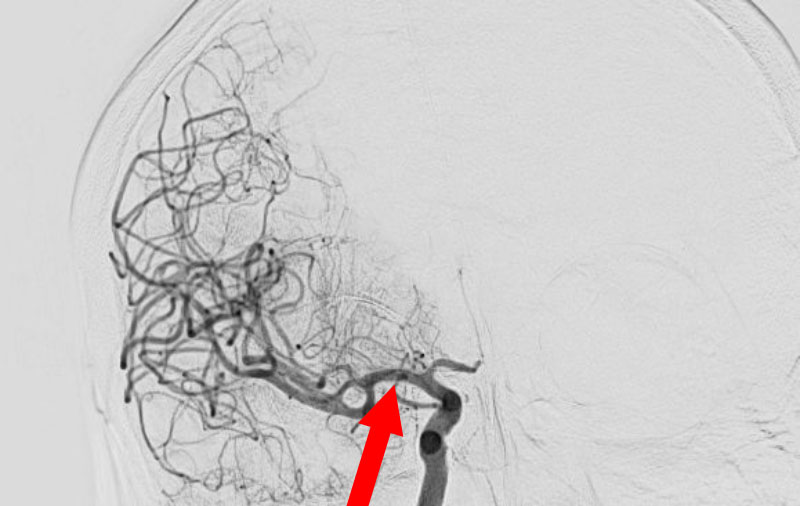

'25年11月

くも膜下出血

右内頚動脈後交通動脈

分岐部動脈瘤破裂

60代

救急外来

No.1593 手術前